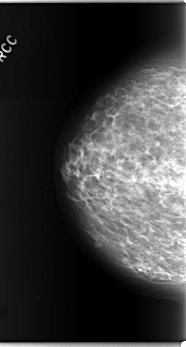

C_0280_1.RIGHT_CC

RIGHT_CC LINES 5888 PIXELS_PER_LINE 3152 BITS_PER_PIXEL 12 RESOLUTION 50 NON_OVERLAY